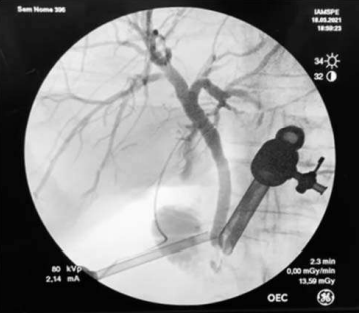

A principal indicação do exame acima seria

avaliar a presença de obstrução biliar.

avaliar a presença de anomalia de via biliar intra-hepática.

prevenir lesão da via biliar.

prevenir fístula biliar.